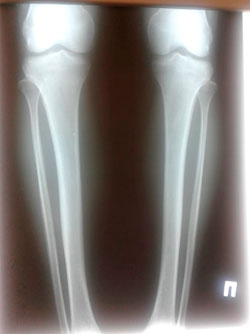

Исходник - 21 год.

Дата операции - 22.09.2020

image-23-09-20-11-35.jpg

image-23-09-20-11-35-5.jpg